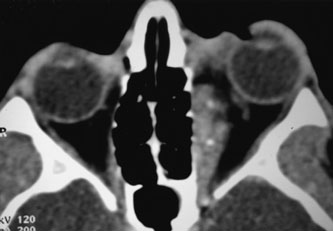

Contrast-enhanced CT of the orbits with direct and coronal cuts is the radiologic study of choice for these patients.45 A well-demarcated, encapsulated oval or rounded mass is revealed, which is typically intraconal in the lateral part of the middle third of the orbit (Fig. 5) but occasionally may extend to the extraconal space.42 Septa within the tumor may be apparent on high-resolution CT. The posterior pole of the globe frequently is indented by the rounded anterior margin of the tumor.42 The optic nerve typically is displaced rather than surrounded by the tumor. Subtle outward bowing of the lateral orbital wall or increase in orbital size may be present, consistent with a long-standing, slowly growing mass lesion.10,42 Enhancement with intravenous contrast occurs and may be homogeneous or inhomogeneous.10,45 Rarely, cavernous hemangiomas may occur as an intraosseous tumor within the orbital or facial bones.42,53–55 Although usually an isolated intraorbital lesion, multiple lesions in one orbit occurred in 8 of 164 (5%) patients of three combined large studies,10,42,45 and bilateral multiple cavernous hemangiomas also have been described.56 In contrast to patients with venous flow malformations in which phleboliths are common, phleboliths are rare in cavernous hemangiomas. Three large studies comprising 164 patients with cavernous hemangioma all reported that no calcification was detected within the tumor.10,42,45If the diagnosis is still unclear or if better definition of details and localization of the lesion is required, then MRI should be performed. Magnetic resonance imaging demonstrates nonspecific characteristics of a lesion isointense to muscle and gray matter on T1-weighted images and hyperintense on T2-weighted images (Fig. 6).57 The lesions show initial central patchy enhancement, which fills up homogeneously within 20 to 60 minutes.58 If ultrasonography is performed, B-scan ultrasonography shows a well-circumscribed mass with a sharply defined anterior acoustic border.23 A-scan ultrasonography shows high reflectivity of the echo signals resulting from the multiple blood-filled vascular channels, regular internal structure with a higher anterior and posterior spike marking the capsule, and moderate sound attenuation (angle of decrease of the echo spike within the lesion).24 Arteriography is not indicated.

Fig. 5. Cavernous hemangioma. Contrast-enhanced axial computed tomography scan shows a well-demarcated, oval intraconal mass in the lateral part of the middle third of the orbit. Note the enhancement within the lesion, which in this instance is inhomogeneous, but can also be homogeneous.